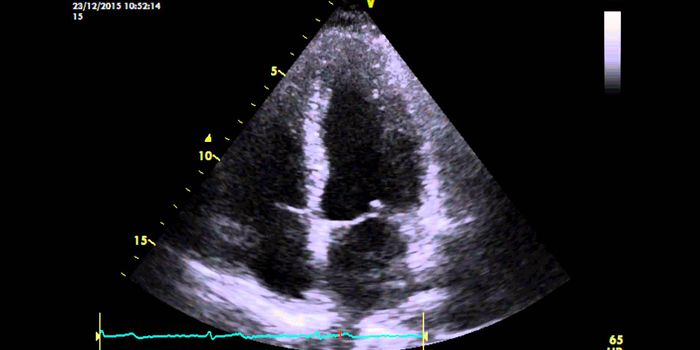

FEB 15, 2017CardiologyThe heart’s four chambers, made up of left and right atria and ventricles, work together in an amazingly intricate ...